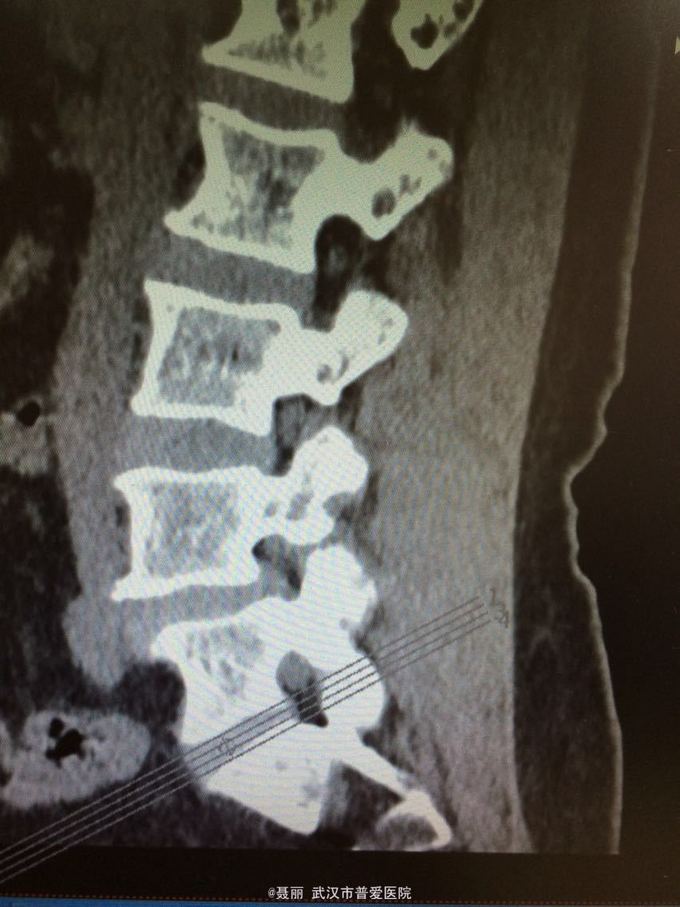

患者,女,61岁 因腰部疼痛,伴左下肢酸胀、疼痛、麻木5月余入院。 患者约5月前无明显外伤等诱因感腰腿疼痛不适,以腰部及左下肢为主,活动后左下肢疼痛加重,休息可缓解。 既往病史:既往体健,否认高血压、糖尿病等其他传染病史,否认食物药物过敏史。

辅助检查:2015年2月27号到我院拍腰椎MRI检查提示:L4椎体Ⅰ-Ⅱ度滑脱,腰椎退变。

初步诊断:腰椎滑脱症 治疗计划:1、完善相关检查:胸片、心电图,血常规,尿常规,肝肾功能电解质、术前全套 2,活血化瘀扩管治疗。卧床休息。 L4滑脱复位+L4/5椎间盘摘除、椎管减压+椎间cage3植骨融合术